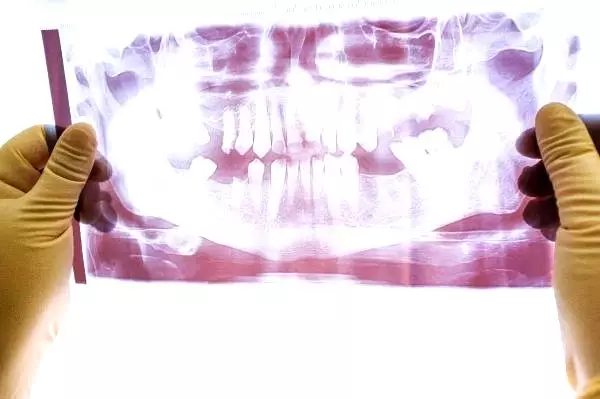

Yapılan bir araştırma sonucuna nazaran Türkiye‘deki nüfusun yüzde 50 ila 70’inin ‘Çene Eklem Rahatsızlığı’na sahip olduğu ortaya koyulurken bu rahatsızlığın en fazla bayanlarda görüldüğü söz edildi.

İstanbul Aydın Üniversitesi Diş Hekimliği Fakültesi Ortodonti Ana Bilim Kolu’ndan Dr. Öğr. Üyesi Ahmet Karaman, Türkiye’de gerçekleştiği ‘Farklı Dişsel Çapraşıklığa Sahip Ortodonti Hastalarında Çene Eklemi Rahatsızlıkları ve Ağız Sıhhati ile Alakalı Hayat Kalitesi Ortasındaki Münasebetlerin Değerlendirilmesi’ isimli klinik çalışmasıyla değişik bulguları ortaya koydu. Karaman’ın klinik araştırmasına nazaran Türkiye’de nüfusun yüzde 50 ila 70’i çene eklem rahatsızlıklarına sahip. Araştırmaya nazaran ‘çene eklem rahatsızlıkları’ bayanlarda daha sıklıkla görülüyor.

Çene eklem rahatsızlığının tek bir bozukluktan ötürü oluşmayacağının altını çizen Karaman, “Çene eklem rahatsızlığı; diş kaybı, kapanış bozuklukları, travma, gerilim, çiğneme, kas yorgunluğu, diş sıkma ve gıcırdatma üzere birçok faktör ile bağlıdır. Türkiye’de nüfusun yaklaşık yüzde 50- 70’inin ömrünün bir periyodunda en az bir çene eklem rahatsızlığı ile ilgili bir bulgu ya da semptoma sahip olduğunu söyleyebiliriz. Çene eklem rahatsızlığının kimi klinik bulguları ağrı, ağzı açıklığında kısıtlanma, çene ekleminde ses ve çiğneme zahmetinden oluşturmaktadır. Ağrıya bağlı çene eklem rahatsızlığı, bireyin günlük faaliyetlerini, psiko-sosyal fonksiyonelliğini ve ömür kalitesini etkileyebilmektedir” tabirlerini kullandı.

Bayan hastalarda çene eklem rahatsızlıklarının daha sıklıkla görüldüğünü belirten Dr. Ahmet Karaman, “Dişsel çapraşıklık ölçüsünün arttığı bireylerde çene eklem sesi görülme oranı daha yüksektir. Ayrıyeten hastaların dişsel çapraşıklık ölçüsü arttıkça çene eklem rahatsızlıkları da artmaktadır. Çene eklem rahatsızlığı şikayeti olan hastalar ömür kalitelerinin düşmemesi ve ileride daha değerli sıkıntılarla karşılaşmamak için uzman diş tabiplerine muayene olmayı göz arkası etmemelilerdir” dedi.